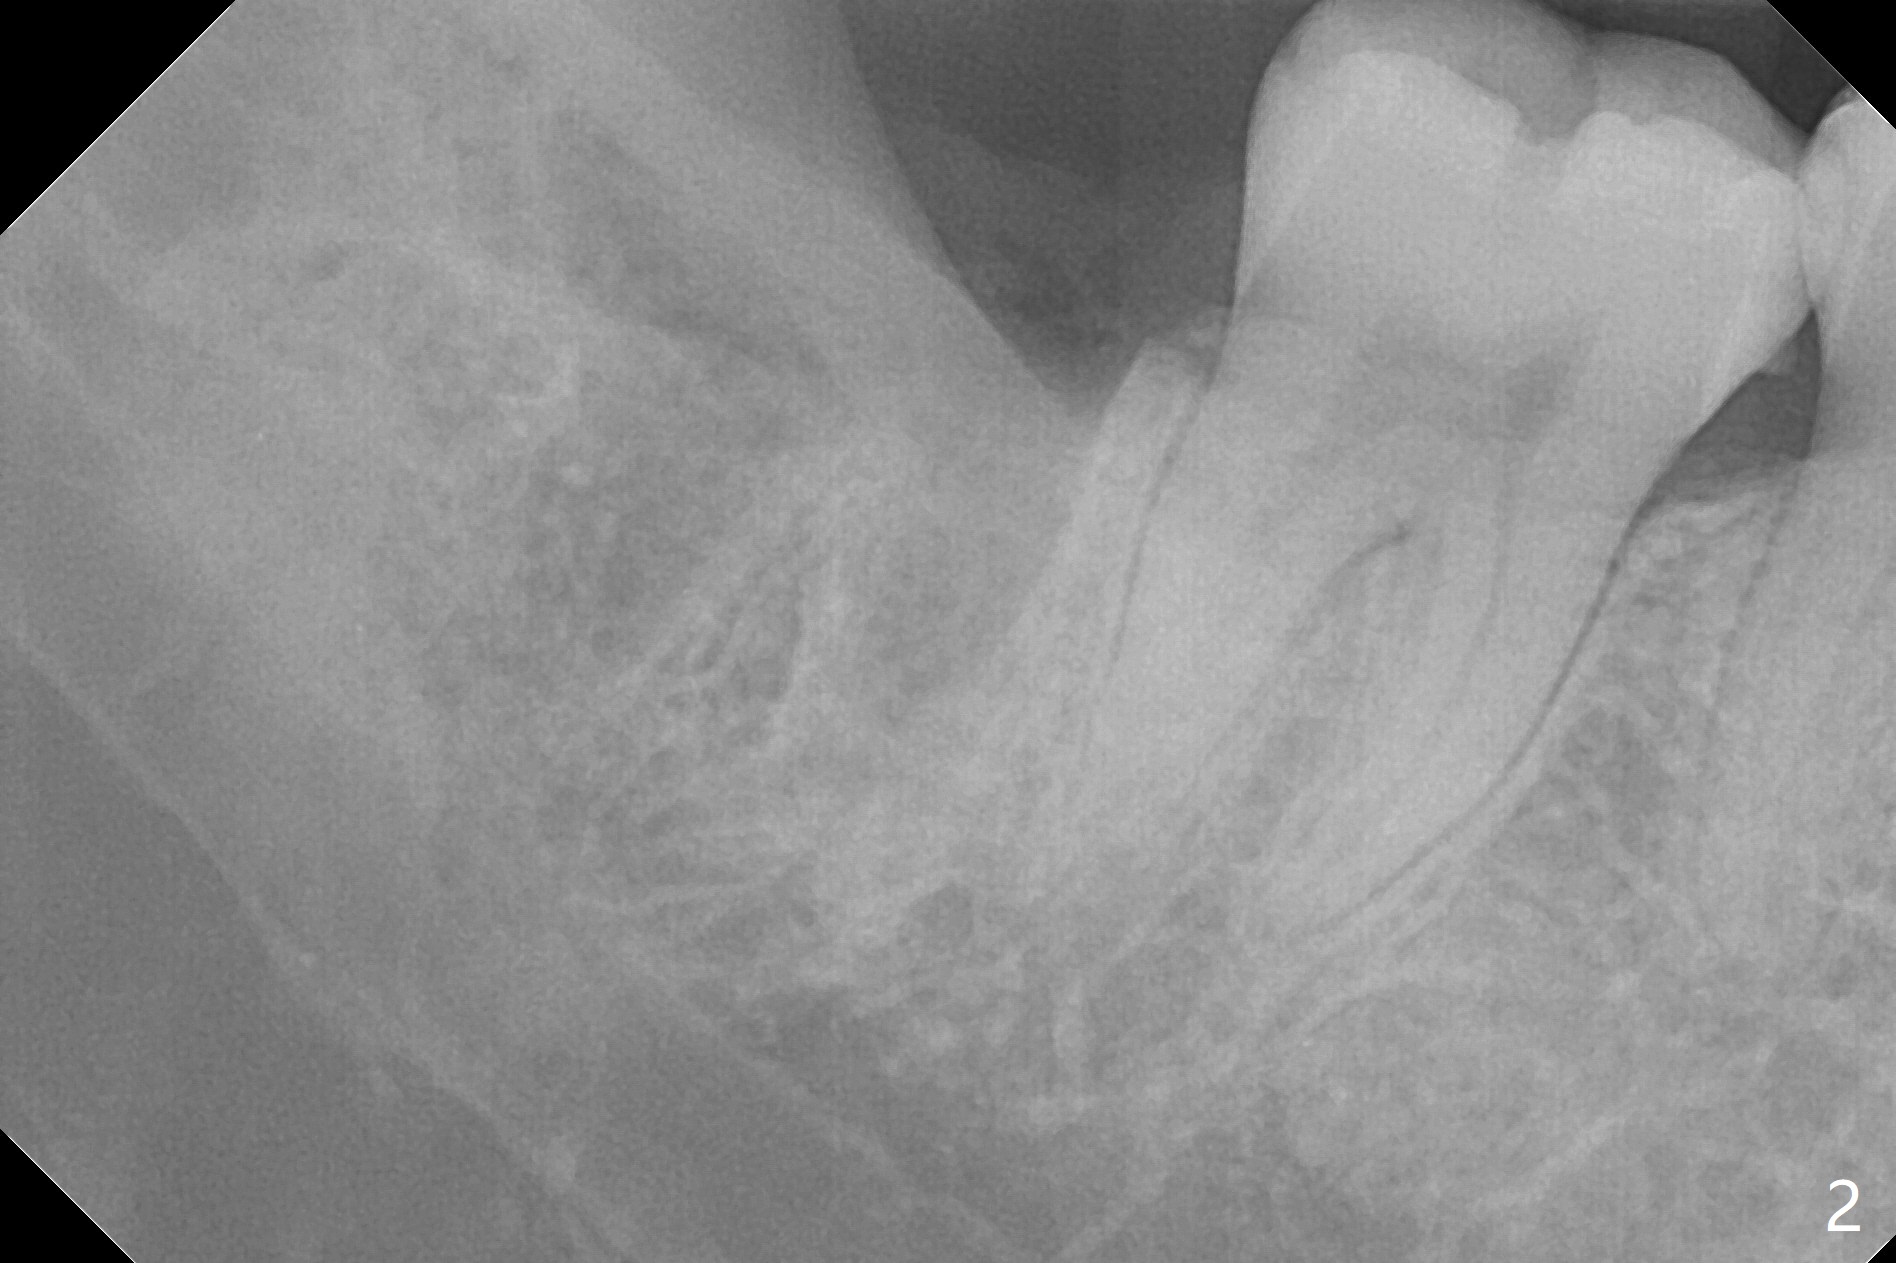

A 35-year-old woman has pericoronitis distal of #32. The bone between the 2nd and 3rd molars is high, but thin (Fig.1 <). With incision, buccal trough is created at #32 for elevators so that the 2nd molar is not affected by elevation. Collagen plug is placed in the socket to prevent dry socket (Fig.2). The mesial socket is completely ossified (Fig.3 *), while the distal one partially ossified 4 months postop. The ossification in the distal socket seems to be from coronal to apical (Fig.3 arrow), in contrast to the traditional thinking of apico-coronal.